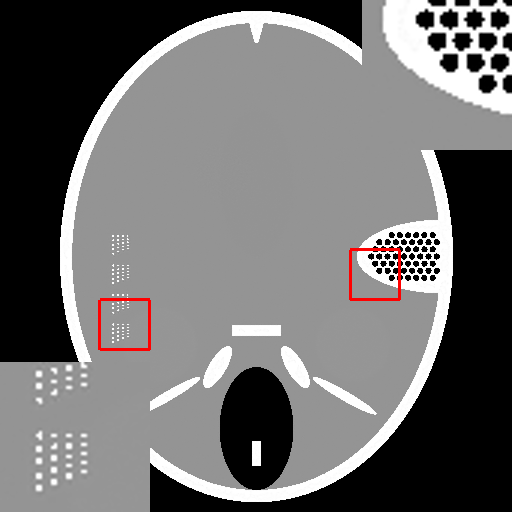

Fig.4 shows the limited-angle CT reconstruction results of the Forbild phantom using different methods, where the projection angle goes from to with increments. Fig.4a presents the reconstruction result of the steepest descent algorithm. Due to the missing projections, the reconstruction result suffers from severe artifacts. Fig.4b shows the result of the CDIP algorithm using Fig.4a as input. It is evident that CDIP cannot remove the existing artifacts in Fig.4a and, in fact, further degrades the reconstruction accuracy. On the contrary, the output of the original DIP method (Fig.4c) significantly suppresses the artifacts and achieves a much better result. Finally, Fig.4d shows the reconstruction result of our proposed method (SDIP), which is very close to the ground truth. Its details will be introduced in Section III-C.

(a) Steepest Descent (23.29dB)

(b) CDIP (19.82dB)

(c) DIP (29.88dB)

(d) SDIP (38.61dB)